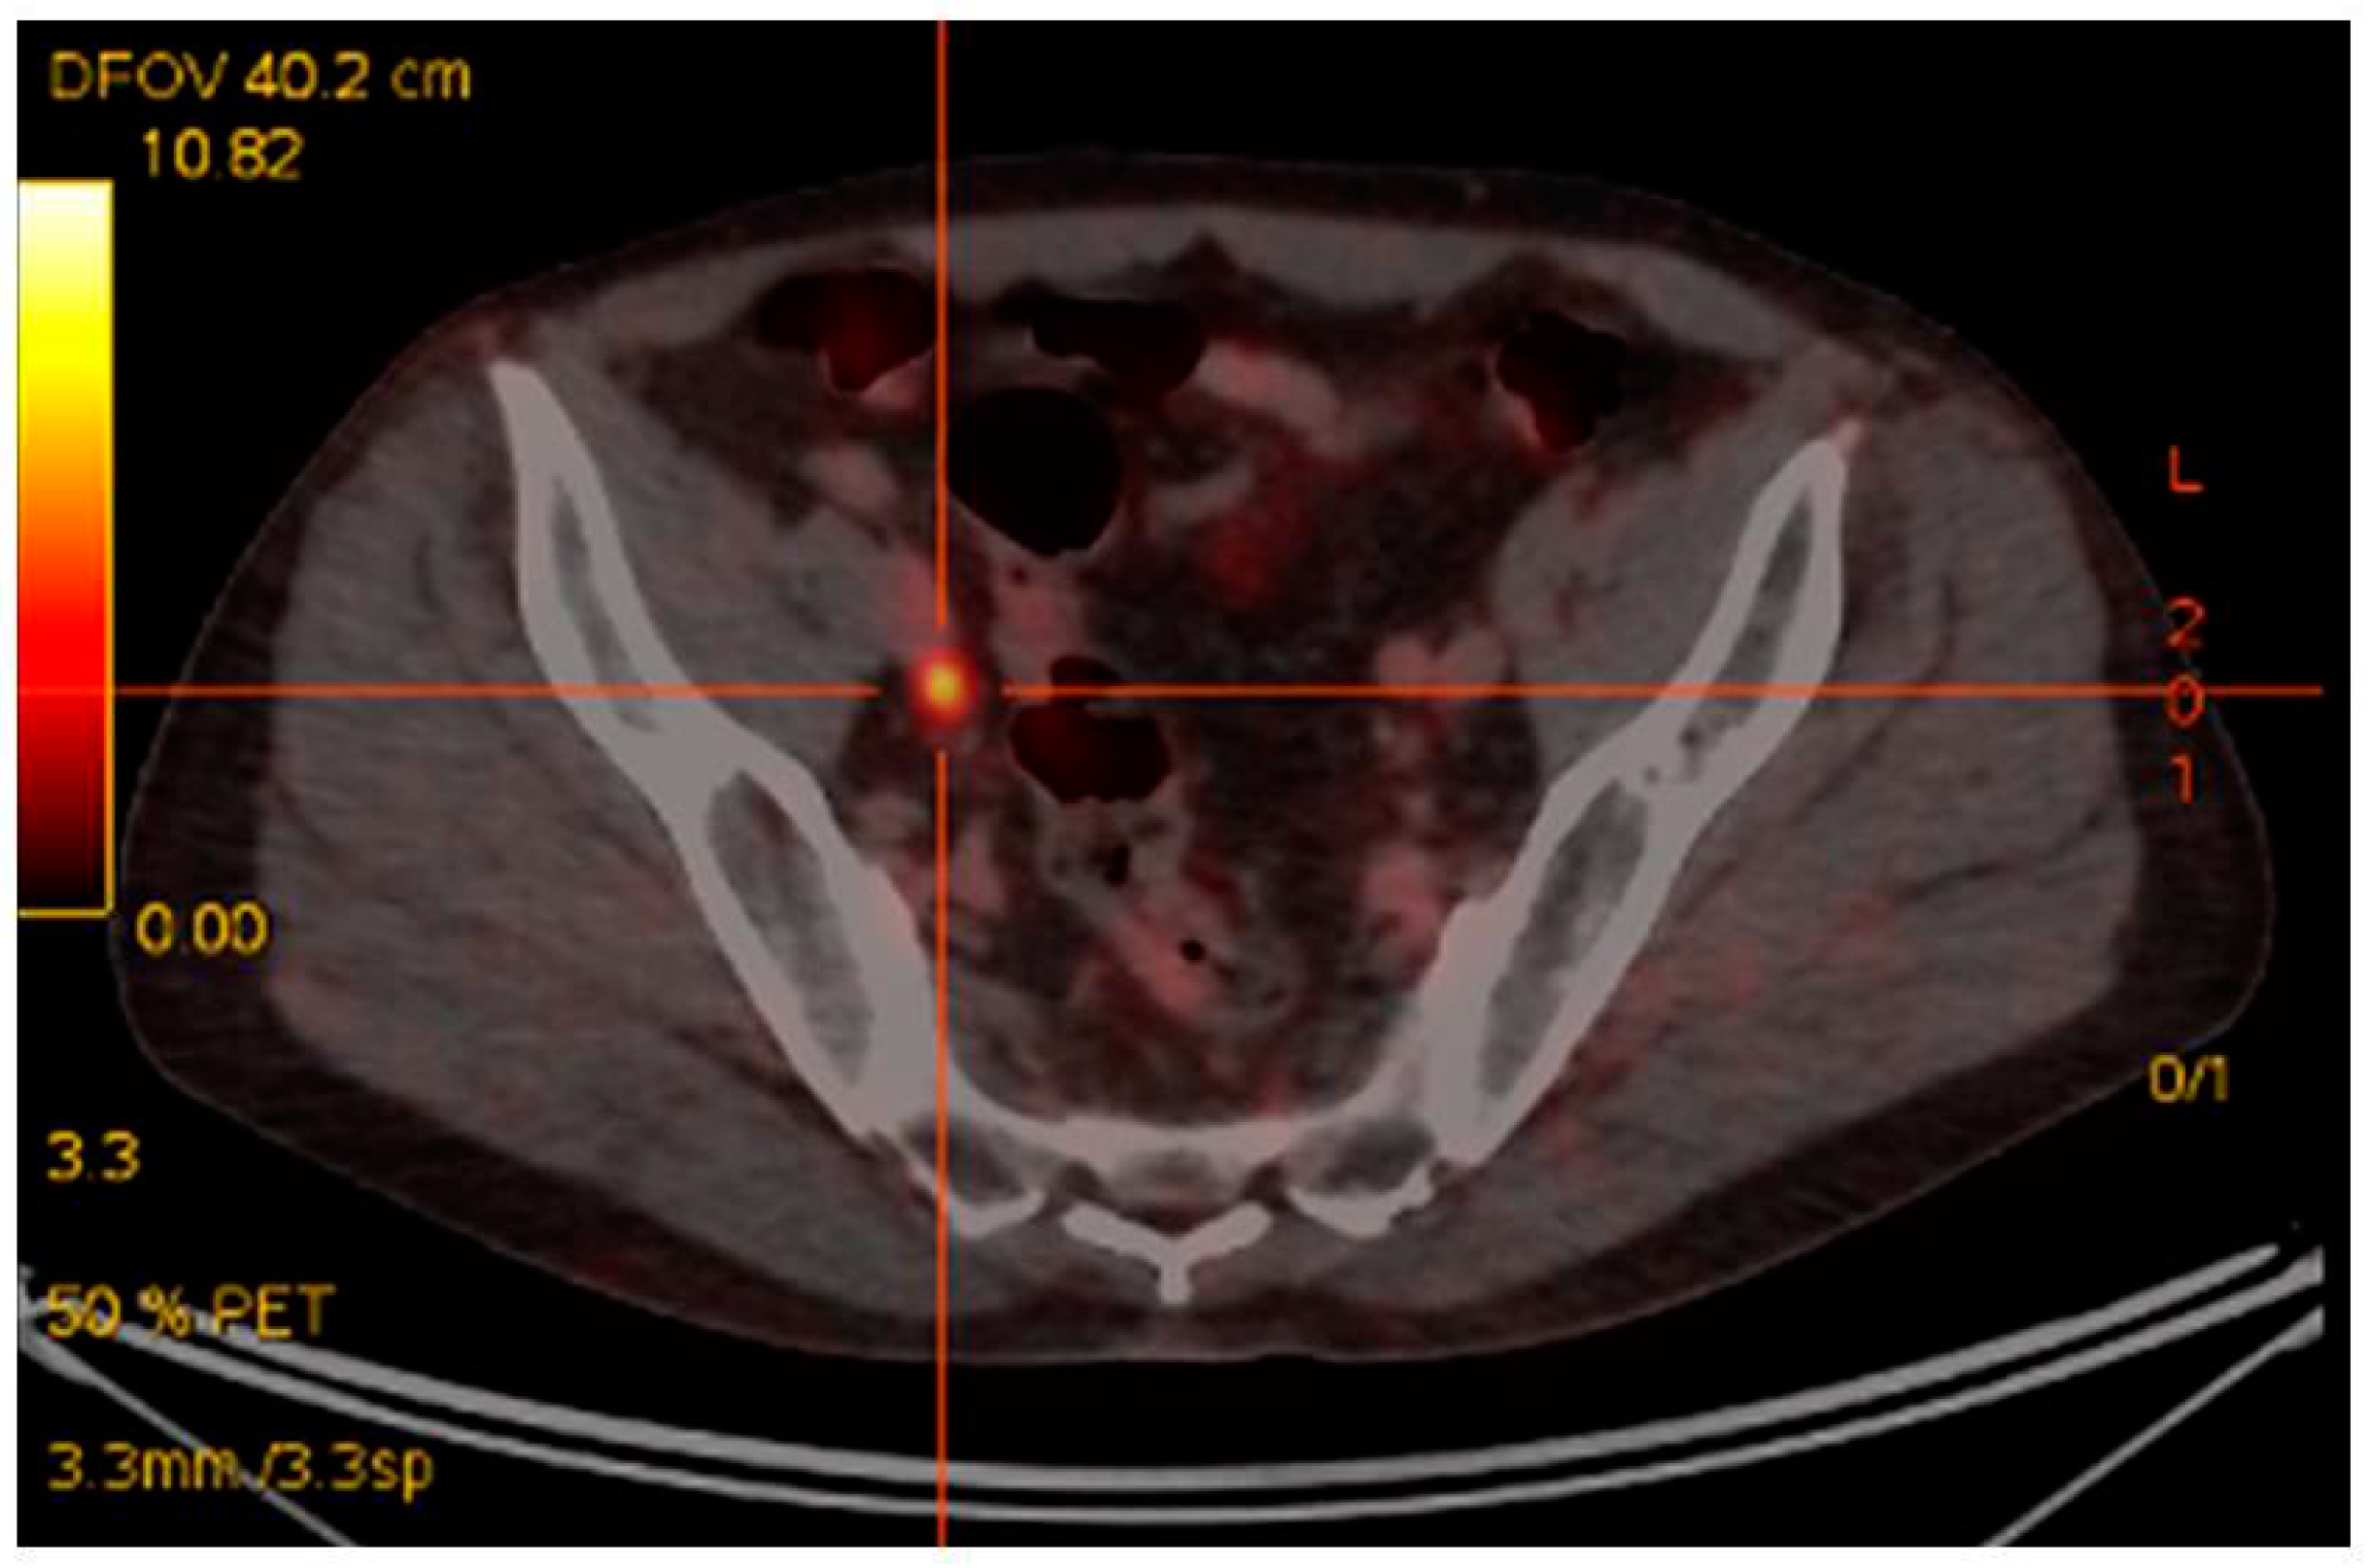

The earliest, and most extensive, experience with 68Ga-PSMA PET/CT imaging has been in the most common clinical scenario of biochemical relapse post-definitive primary therapy [60]. Up until the advent of 68Ga-PSMA PET/CT the mainstay of imaging included CT +/− bone scintigraphy and in some cases MRI [20]. The largest retrospective study of 1007 patients, reported detection rates for 68Ga-PSMA-11 PET/CT of 79.5%, in the setting of biochemical recurrence [61]. A recent meta-analysis revealed detection rates with 68Ga-PSMA PET/CT of 58% in patients with PSA between 0.2–1.0 ng/mL, 76% for PSA between 1 and 2 ng/mL and 95% for PSA > 2.0 ng/mL [62]. These findings reflect our own single institutional dataset utilizing 68Ga-PSMA I&T in 150 consecutive patients, where we have seen PSMA-avid disease in the setting of biochemical relapse in 25% of patients with PSA < 0.5 ng/mL. 67% of patients with PSA 0.5–1.5 ng/mL and in 92% of patients with PSA > 1.5 ng/mL [63]. Importantly, 68Ga-PSMA-I&T PET/CT reveals, in many cases, metastatic disease that is considered occult on CT, as demonstrated in Figure 1. In our dataset, statistically significant differences were seen between recurrent disease demonstrated by 68Ga-PSMA I&T and diagnostic contrast CT detection rates [63]. When compared with histological diagnosis, specificities of up to 100% have been detected in pre-surgical nodal assessment prior to nodal salvage surgery using 68Ga-PSMA [64,65]. A recent prospective Australian multi-center trial has shown that 68Ga-PSMA PET/CT leads to a change in management intent in 62% of patients with biochemical relapse, based upon the PSMA PET/CT scan result [66]. A separate study of 131 patients showed 68Ga-PSMA HBED PET/CT had a clinical impact in 76% of patients imaged [67].

Figure 1.

Rising PSA post-prostatectomy. PSA 0.9 ng/mL. CT unremarkable. 68Ga-PSMA-avid right pelvic lymph node.